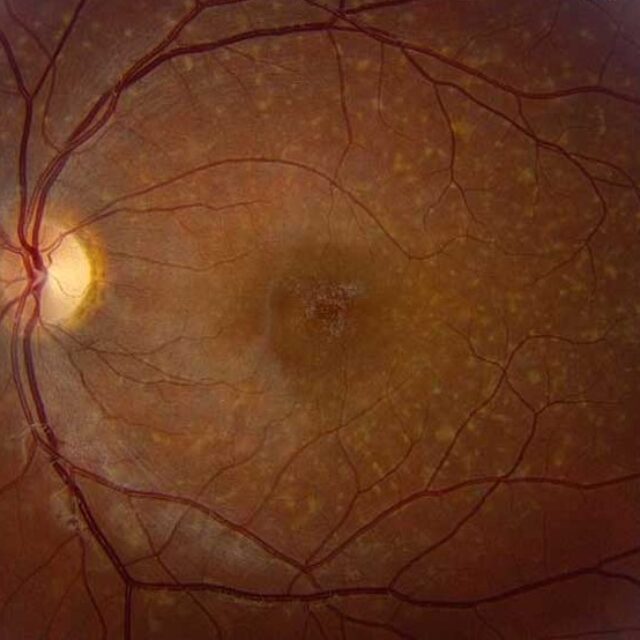

Лікар зустрічається зі складністю диференціації ознак, викликаних самою операцією, та викликаних інфекцією. Деякі ознаки пост-травматичних ендофтальмітів є дуже характерними і вказують на конкретний мікроорганізм. Кільцевий рогівковий абсцес ймовірно означає інфікування Bacillus cereus. Газ всередині очного яблука може бути як ознакою проникаючого поранення, так і інфікування газоутворюючими організмами, такими як види Clostridium.

Кільцевий рогівковий абсцес